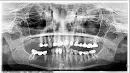

Добрый день! 04 Января удалили зуб (4 справа на нижней челюсти, была гранулема, лечение не помогло), после чего был отек и большой синяк. Во время удаления сделали 3 укола анестезии, т.к. не действовала. До сих пор не проходит онемение нижней губы и челюсти, но не смотря на онемение, от центра подбородка по направлению к нижней губе постоянно чувствуется боль, покалывание, жжение и немного больно трогать челюсть. Лечащий врач говорит, что все нормально, и через месяц должно пройти. После удаления пила лейкомицин, сейчас уже 10 дней, как принимаю нейромультивит. Нужно ли ждать месяц или стоит обратиться еще к какому-нибудь специалисту (стоматологу, хирургу, невропатологу)?

Прикрепленые фото